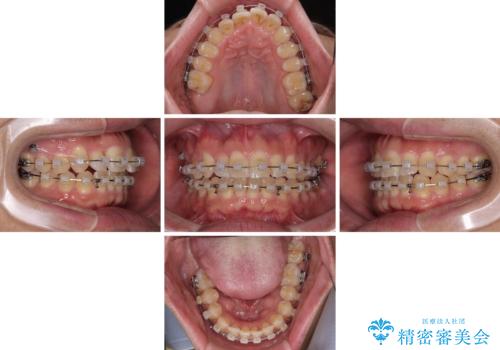

- 上下前歯のデコボコを気にして来院された患者様です。

ワイヤー矯正でもマウスピース矯正でも可能でしたが、短期間で、自身の手を煩わせることなく治療を行いたいとのことで、ワイヤー装置にて矯正治療を行うこととしました。

上顎前歯の舌側転位が顕著であったため、治療期間が長くなると思われましたが、僅か1年で無事に終えることができました。